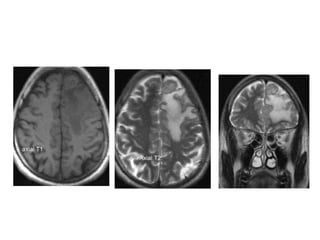

MRI BRAIN :AXIAL SECTIONS

Post Contrast Axial MR Image of the brain

Fig. 1.6 Post Contrast Axial MR Image of the brain

Post Contrast sagittal T1 Wtd

M.R.I.

Section at the level of Thalamus